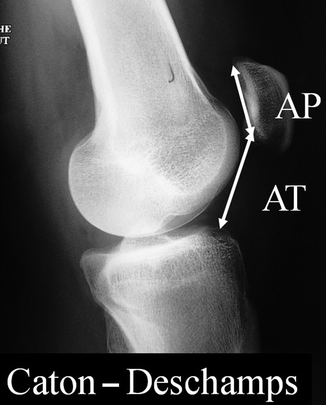

WebJul 28 2022 The Caton-Deschamps index is used to measure patellar height and identify patella alta and patella baja. Ordena directo desde la. Coxa valga deformity is a common pathologic.

Les comarques dalta muntanya en canvi destaquen per prescindir del peix i marisc i lús de larròs també és més aviat testimonial. The Caton-Deschamps index relies upon the length of the patellar articular surface and its distance from the tibia reducing erroneous measurements in those with long patella bodies as measured in the Insall-Salvati ratio. Complications involving the extensor mechanism after TKA are potentially disastrous.